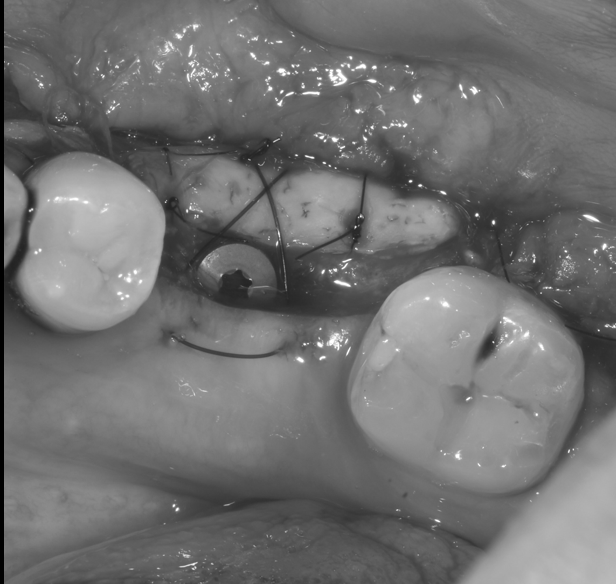

【池袋|歯肉退縮の治療】結合組織移植術によるル...